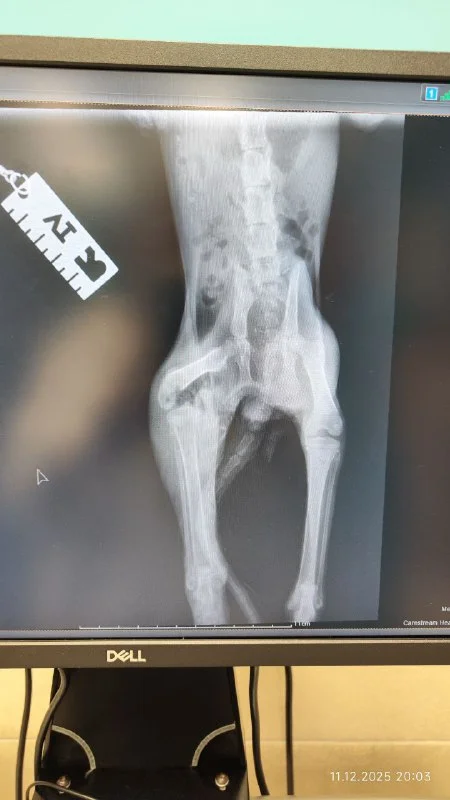

Здравствуйте. Прошу помощи с котенком. Нашла в тяжёлом состоянии. Сейчас наблюдается у доктора Христоса в Small animals. После вскрытия абсцесса и нескольких дней антибиотиков у него появились силы двигаться и жалобно мяукать. Операция предстоит в субботу. Но, инфекция продолжает разрушать кость. Если она остановится, то которебенку наложат скобу ,если нет ,то ампутация задней лапы. Котенок уличный, у меня есть возможность выходить его и выпустить на улицу после того ,как лапка заживёт, но нет возможности его взять к себе ,если лапу ампутируют, а на улице он не выживет без неё. И тогда выход усыпление, чтобы не мучить живое существо. Если в субботу не найдется добрый души человек, кто может трехлапого взять себе,то его усыпят. Я готова взять расходы на себя по операции, восстановлению, прививкам, но тщательно подумав и всё взвесив, я не могу его оставить себе .

позвонили из клиники, хоть вчера котенку было лучше, сегодня он совсем плох, видимо пошло заражение крови. Спрашивают усыплять сейчас или оставлять до завтра?

У котенка гипотермия и так как инфекция уже в кости говорят что также заражение крови. Он получает антибиотики и под капельницей, но если его состояние не улучшится операцию сделать не смогут, так как он не сможет перенести наркоз. Также говорят может потребоваться переливание крови.